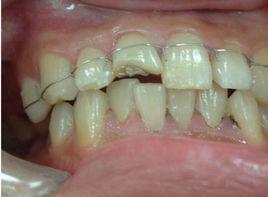

主要是利用細不鏽鋼結紮絲將患牙結紮在一起,並固定於健康穩固的鄰牙上。首先取直徑為0.25mm不鏽鋼絲一段,長度以水平圍繞所要固定的牙齒唇面和舌面再延長125px為宜。將鋼絲從固定牙齒的遠中間隙穿入,經舌隆突再由該牙近中間隙穿出,結紮絲的位置應在舌隆突與鄰面接觸點之間,以防止鋼絲滑脫或滑入齦緣以下,對牙齦造成刺激和損傷。把鋼絲拉緊在近中牙間隙處扭結,鉸結多少可根據牙間隙的寬窄決定,若間隙很小,也可不作扭結,僅做一“8”字形交叉,再結紮另一個牙。結紮鋼絲扭結程度要適當,不能產生改變牙齒原來位置的矯正力。將鋼絲兩端分別由牙間隙中呈∞形穿出穿進,一直終止於健康牙上。鋼絲末端絞緊,剪去多餘鋼絲,斷端彎向牙齦方向,置於牙間隙內,以免在咬合咀嚼過程中鬆脫移位,並應注意切勿刺激牙齦及唇頰黏膜。必要時可加用釉質粘合劑或複合樹脂,加強結紮的穩固。也可使用結紮絲暫時性固定鬆動牙齒,即取適當長度的細不鏽鋼絲,彎製成弓形,與所需固定牙齒的外形一致,在每一牙間隙處利用一段段短的不鏽鋼絲拴結固定,而非主絲自身扭結。

結紮後應檢查咬合關係,防止咬在鋼絲上。在臨床上如發現有早接觸,則應進行咬合調整。結紮絲應儘量不妨礙患者口腔衛生措施的實施,應對患者加強口腔衛生宣教,教會在結紮的情況下如何控制菌斑。一般可用牙間隙刷清潔鄰面,並注意刷淨舌側牙面等。可用於外傷或牙周術前暫時性固定。

1.3不鏽鋼絲聯合複合樹脂暫時性牙周夾板

按照上述方法用細不鏽鋼結紮絲將患牙結紮在一起後,在牙齒唇舌鄰面可覆蓋樹脂製作鋼絲與複合樹脂聯合夾板。或將0.4mm不鏽鋼絲,彎製成弓形,與所需固定牙齒的舌側外形一致。牙面酸蝕、塗布粘接劑,光照後,用複合樹脂將預彎的鋼絲固定在兩側健康牙上,光照固化後,表面再覆以樹脂,光照固化,形成類似鋼筋水泥狀結構。這兩種方法都是利用鋼絲和複合樹脂的雙重固定作用,與單純使用樹脂或鋼絲相比,較牢固,維持時間較長。可用於固定牙周治療後鬆動仍較明顯的前牙,尤其是下前牙。